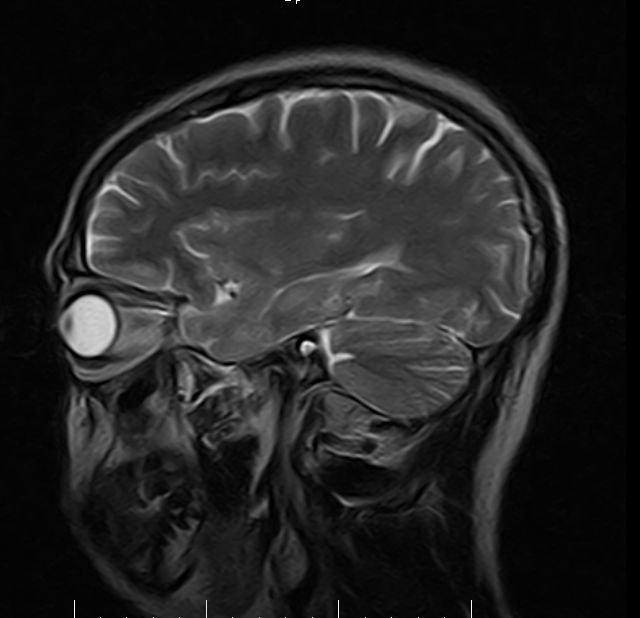

标题: MRI2379:30岁,男,癫痫10年,请各位看一下;CT示:左颞叶钙 [打印本页]

左颞叶区见不规则点状混杂信号影

考虑左侧颞叶脑血管畸形(avm)。----t1低等高混杂信号,t2等高信号周边较多流空血管影[冠状位明显],mra左侧大脑中动脉受压,远侧聚集.